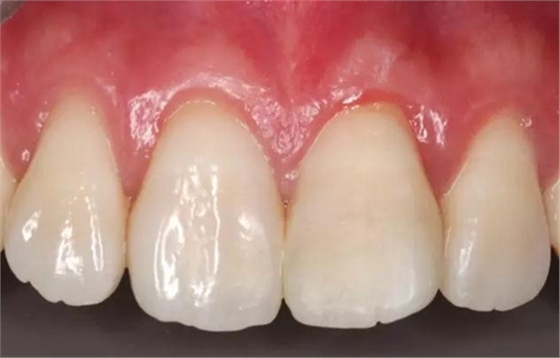

術(shù)后即刻口內(nèi)照

口內(nèi)檢查:21切端牙體色澤恢復(fù),唇側(cè)面見水平向粘接界面,殘留少許樹脂水門汀,牙齦腫脹較前消退,叩-,松-。

患者1個(gè)半月后復(fù)診,口腔衛(wèi)生狀況保持良好,牙齦健康,折斷線不可見。